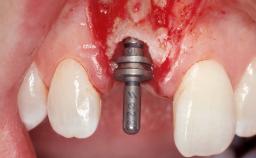

A 33-year-old female patient presented with an upper left central incisor that required extraction after a failed endodontic therapy. The tooth had been traumatized when the patient was a teenager and had undergone several endodontic treatments, including two apicectomy procedures. The patient was in good health and did not smoke. Clinical examination showed that the patient had a high lip line. In full smile, the gingival margins of the upper teeth were visible to the first molars. The gingival margins of central incisors 11 and 21 were only just showing. Examination of tooth 21 confirmed that the tooth was mobile and had hypererupted by 1 mm.

Placement Protocol Immediate implant placement

Tooth Site Maxillary incisor or canine

Socket Morphology Single-root socket

Socket Integrity Damage to one or more bone walls

Bone Volume Damage to one or more socket walls

Type of Implants One-Piece